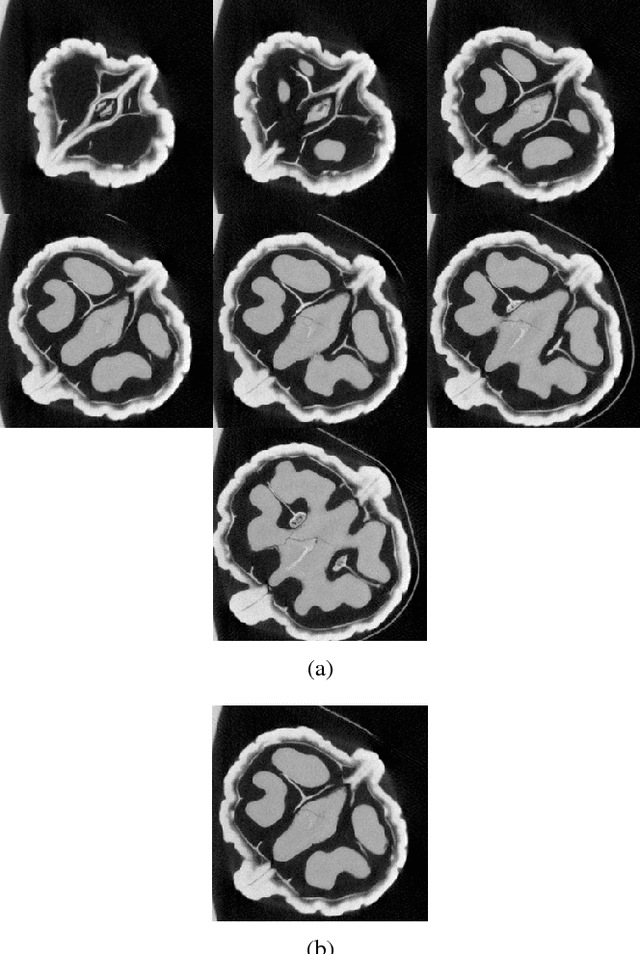

Abstract:Recent research in tomographic reconstruction is motivated by the need to efficiently recover detailed anatomy from limited measurements. One of the ways to compensate for the increasingly sparse sets of measurements is to exploit the information from templates, i.e., prior data available in the form of already reconstructed, structurally similar images. Towards this, previous work has exploited using a set of global and patch based dictionary priors. In this paper, we propose a global prior to improve both the speed and quality of tomographic reconstruction within a Compressive Sensing framework. We choose a set of potential representative 2D images referred to as templates, to build an eigenspace; this is subsequently used to guide the iterative reconstruction of a similar slice from sparse acquisition data. Our experiments across a diverse range of datasets show that reconstruction using an appropriate global prior, apart from being faster, gives a much lower reconstruction error when compared to the state of the art.